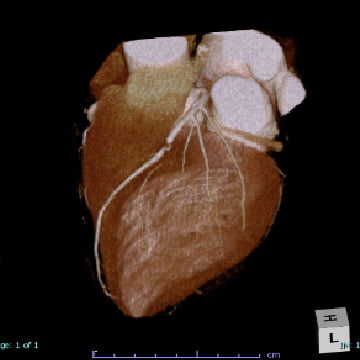

心臓CT